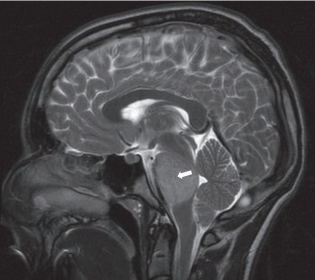

一名6岁的女童在视力检查出现问题后被转介到眼科。经检查,她的左眼视力下降(20/80)和色觉(仅限控制板)。右眼视力和色觉正常。她有一个低振幅,高频摆...